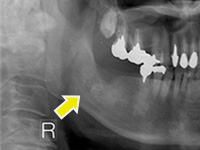

難易度の高い親知らずの抜歯の症例

親知らずが非常に深い位置に、逆さの状態で埋まっていたケースです。右下7番の歯も保存不可能な状態だったため、抜歯しました。